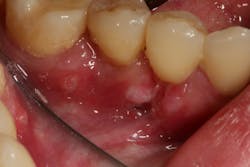

- 5% to 10% of canker sores are herpetiform aphthous ulcers, which are multiple ulcerations 2 mm to 3 mm in size that, when close enough to each other, can coalesce into one large ulcer. These types of canker sores are found on keratinized and nonkeratinized oral mucosa, last 10 to 14 days, and can be very painful (figure 3).

Figure 3: Herpetiform aphthous ulcer (Photo courtesy of Lisa Dowst-Mayo, RDH, BSDH)